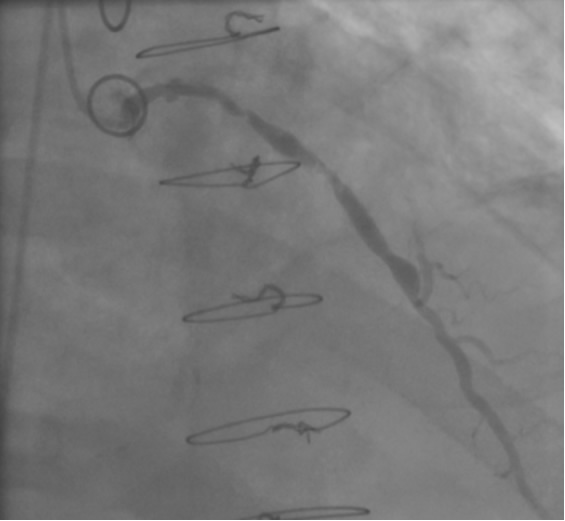

The most commonly used catheters for left heart catheterization and vein graft angiography can be seen in Figure 1 and Figure 4-13. Most of the vein grafts have horizontal take off and can be successfully engaged using a commonly used Judkins right number 4 (JR4) catheter. The JR4 catheter is the most commonly used catheter for the engagement of the right coronary ostium with horizontal take off. However, many vein grafts have unusual take off requiring different catheters. Many right coronary vein grafts have steep inferior take off making the ostial engagement with JR4 difficult or impossible (Figure 10). In such a scenario, a multipurpose catheter which has a shallow angulation is the best choice (Figure 11). The second major challenge in engaging vein graft ostia, particularly vein grafts supplying the left coronary arteries, is the shape of the aorta. A large aorta can make it very difficult for the JR4 catheter to reach the ostial vein grafts. In such a situation, Amplatz (AR) right and left (AL) catheters can be very helpful to reach the vein graft ostia. Amplatz catheters have a larger primary curve and have been used successfully in unusual superior take off of left coronary arteries or vein grafts and in large aorta. Amplatz catheters are available in different sizes (from smaller to larger curve: AR 1, AR2, AL2, AL2 and AL3). Occasionally, a very superior take off of a vein graft requires specially designed bypass graft catheters. Amplatz catheters are also extremely helpful in engaging native right coronary ostium with anterior take off.

PCI of the vein and arterial grafts have unique challenges. For any PCI, guide support is very important for successful balloon and stent delivery. In a tortuous vein graft with a steep angle, advancement of a stent can be very difficult and challenging. Therefore, it is important to choose the best available catheter before starting PCI. Similar to the right coronary angiography, a JR4 guide catheter is most commonly used in this setting. However, Amplatz guide catheters for left vein grafts and multipurpose catheters for right vein grafts are better choices in certain anatomy. In Figure 8 and Figure 10 two examples of poor guide support in two vein graft interventions can be seen. Initially, a JR4 guide was used for PCI of the vein graft supplying the left anterior descending artery (LAD) without any success. However, after changing the guide to an Amplatz left 2 guide catheter, we achieved excellent support without any difficulty in advancing two stents (Figure 9). In Figure 10, difficulty is illustrated in engaging the vein graft ostium supplying the right coronary artery with a JR4 catheter. This vein graft has a very steep inferior take off from the aorta. After changing the guide to a multipurpose catheter, we were able to deliver three stents successfully without any difficulties (Figure 11). Similar challenges exist in the treatment of the left IMA or right IMA. These arterial grafts can be extremely tortuous making stent delivery very difficult. It may be necessary to use short length stents for a better deliverability or stents with lowest profile. Usually, similar to the native coronary intervention, a 6 French guide is appropriate for the routine use.